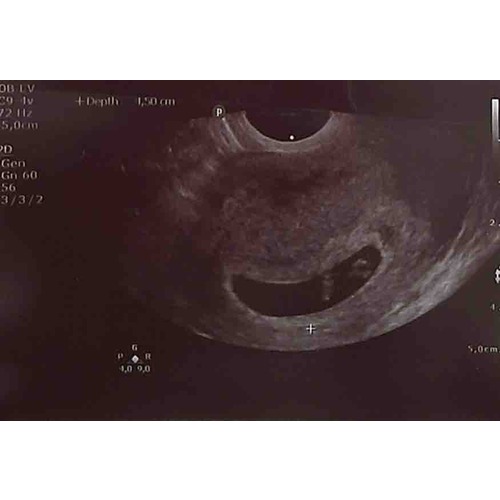

Vruchtzakje 6 Weken Miskraam. Hoe Lang Blijft Een Leeg Vruchtzakje Zitten Bij Een Miskraam? Ik ben afgelopen maandag voor nog een controle geweest (ruim een week na de miskraam) en toen was het vruchtzakje verdwenen Kreeg toen ook de boodschap: of buitenbaarmoederlijke zwangerschap, of wordt een miskraam, of je bent nog niet zo ver

6 weken zwanger Ontdek je symptomen en to do's. Sommige vrouwen merken er weinig van, terwijl het bij andere verloopt als een heftige menstruatie. Ik had 3 dagen na mijn gemiste menstruatie getest en mijn positieve streepje was bijna niet te zien, zo licht! Daarna een clear blue test gedaan en die gaf aan 1/2 weken zwanger

Pin op À acheter. Zolang de temperatuur net iets boven de lichaamstemperatuur van de moeder ligt, kan de vruchtzak het effectiefst te werk gaan Daarom maakt de verloskundige in dat geval altijd een week later nog een echo.